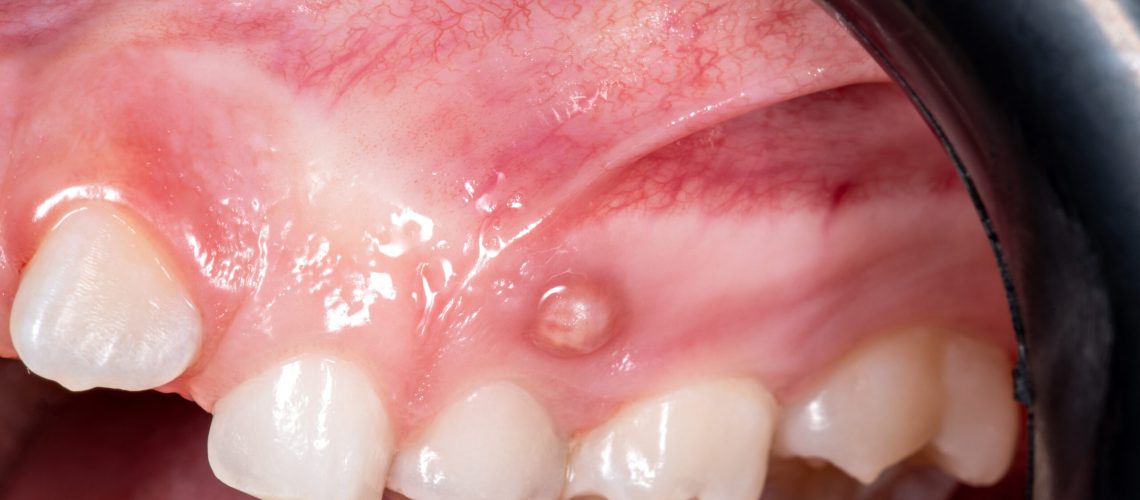

Swollen or inflamed gums can be a sign of underlying dental issues that shouldn’t be ignored. At Polaris Dental Brampton, our experienced team offers effective treatment for swollen gums, including care for refugee claimants covered by the Interim Federal Health Program (IFHP).

• Infections or abscesses

• Red, tender, or puffy gums